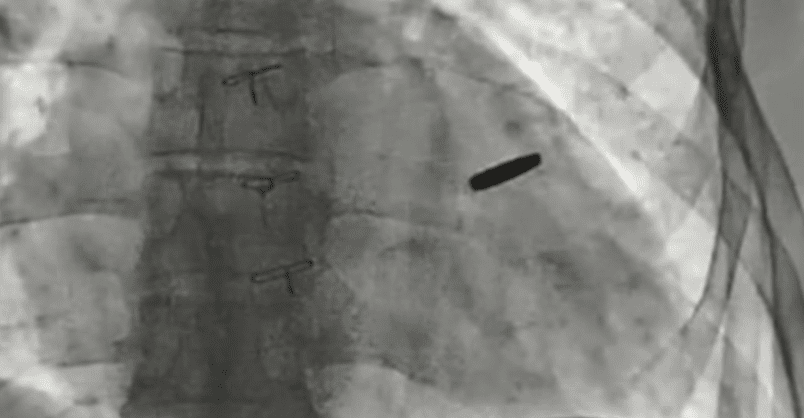

Ukrainian doctors have removed a bullet lodged in the heart of a soldier who defended Mariupol’s Azovstal steel plant and survived three years in Russian captivity, according to Borys Todurov, director of Ukraine’s Heart Institute, on September 19.

Todurov said the bullet miraculously missed vital structures, allowing the fighter to live with it embedded in his heart for three years.

“The bullet has now been removed. The guy got lucky. I think he will live a long and happy life,” Todurov said, holding up the projectile during a press briefing.

He described the soldier as “invincible” and praised his resilience: “Three years in captivity with a bullet in his heart. These people are titans. Unconquerable!!!”

Doctors said the bullet caused no serious damage during the years it remained lodged in the heart.